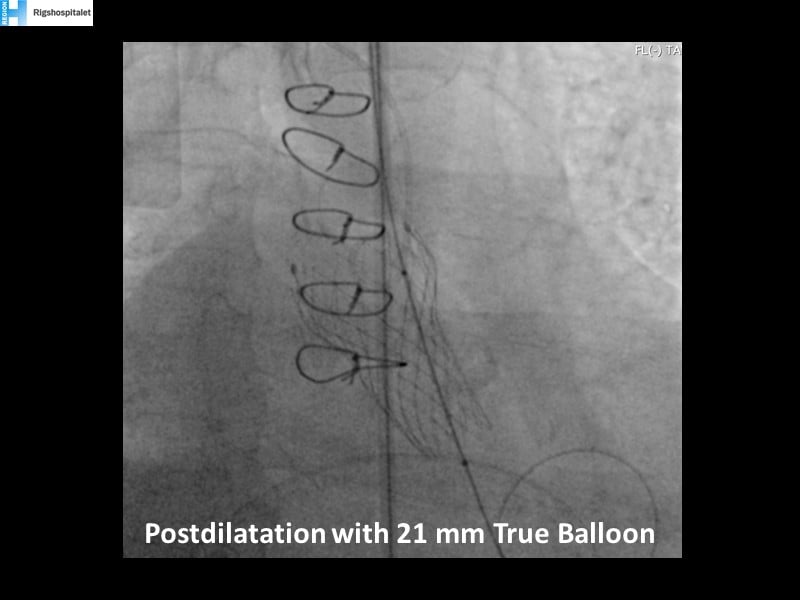

Your most challenging TAVI cases - Achieving precision and control with Evolut platform

How to deal with challenging anatomies? Find answers in this EuroPCR 2022 session with case studies to explore and learn how to achieve optimal patient outcomes with Evolut platform, uncover practical tips and techniques to achieve implant precision and control, and become familiar with technical considerations and procedural execution of TAVI.

- To learn how to achieve optimal patient outcomes with Evolut platform in diverse challenging anatomies

- To uncover practical tips and techniques to achieve implant precision and control

- To become familiar with technical considerations and procedural execution of TAVI